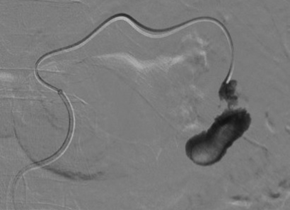

The patient was hemodynamically stable, but with mild tachycardia. He underwent endovascular embolization treatment, in which he was selectively catheterized in the splenic artery and dorsal pancreas (Figure 2). Lipiodol and a controlled-release spring were used to occlude the pseudoaneurysm and dorsal pancreatic artery, maintaining patency of the splenic artery (Figures 3 & 4). At the end of the procedure, there was no extravasation of contrast. During hospitalization, the patient remained in an intensive care bed for 48 hours for hemodynamic surveillance and clinical treatment of post-contrast acute renal failure. The patient was discharged 96 hours after the procedure. Being guided at every hospital discharge to follow up in the outpatient service.

Because it is a rare complication, there are few cases described in the literature showing the diagnosis and management of the condition. In our case, there was therapeutic success through endovascular treatment with glue and controlled-release coils. Thus, the patient was spared an open surgical procedure, prolonged hospitalization and possible intraoperative complications of hostile anatomy due to the history of recurrent pancreatitis. In addition, the patency of his splenic artery was maintained without the use of a stent and consequently maintenance of the spleen.